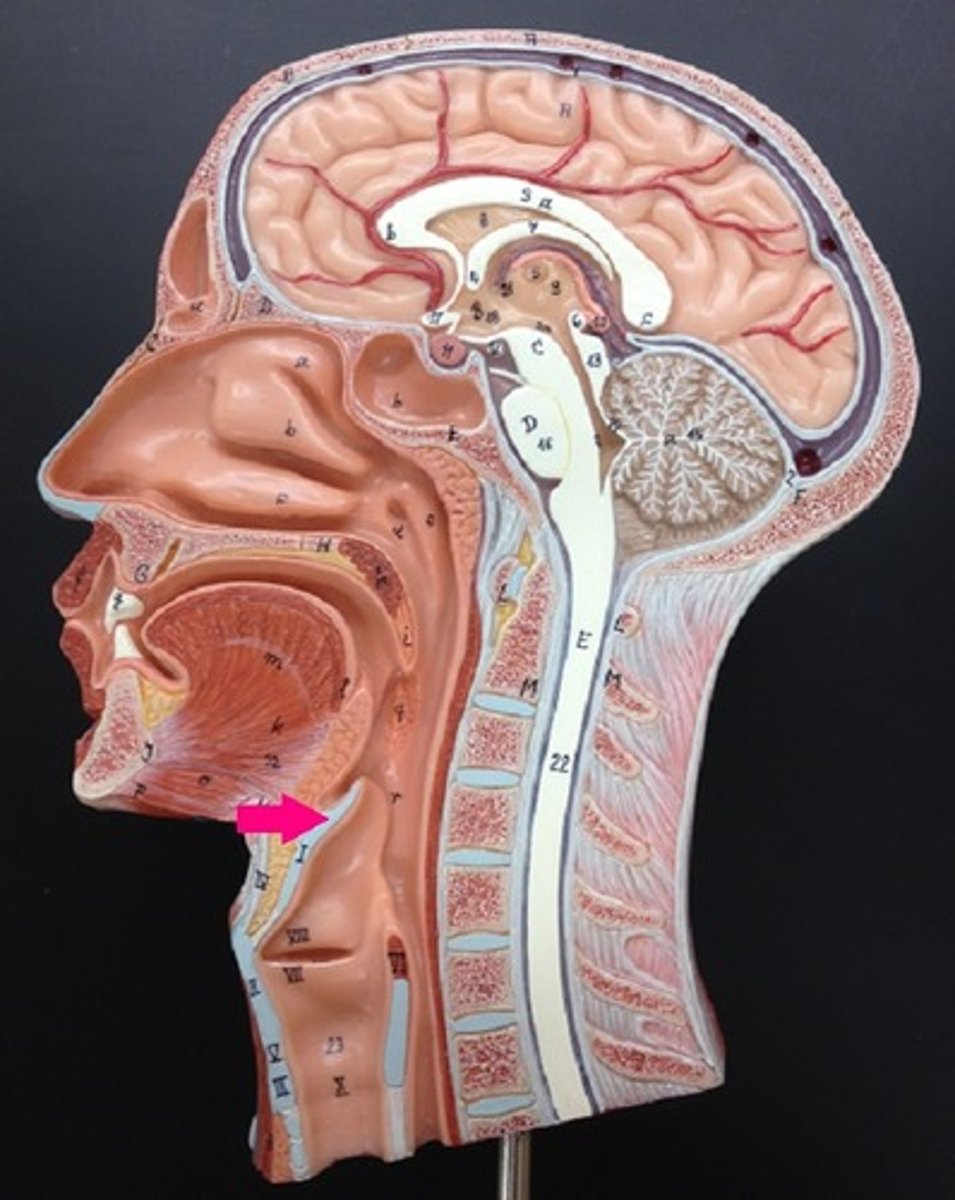

Pharynx

oropharynx

Epiglottis

laryngopharynx